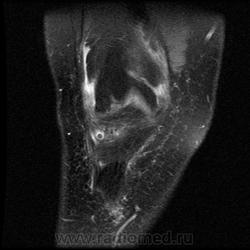

Новообразование коленного сустава ? Коллеги, помогите разобраться, пожалуйста. В передних отделах коленного сустава, спереди от передней интерменисковой связки визуализируется структура, имеющая низкий МР-сигнал во всех последовательностях (Т1-, Т2-ВИ, PD FSEFatSad). Что это может быть?

По клинике: неудачно наступила, почувствовала щелчок. Жалуется на отек коленного сустава. Из сопутствующих патологий на МРТ выявила: ДОА, разрыв заднего рога и тела мед.мениска. Бурсит. Синовит.

Виллонодуллярный синовиит?

Жалобы у пациента есть? Предположил бы хондроматоз.

Вероятно, хондральные тела.

Соглосна, похоже на то!